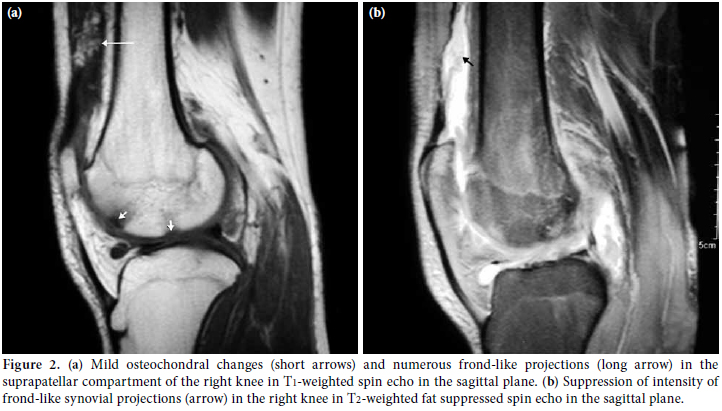

Magnetic resonance imaging revealed a large effusion and numerous frond-like projections which were prominent in the suprapatellar compartment of right knee. The intensity of these frond-like synovial projections, which were suppressed in fatsaturated sequences, was similar to the intensity of fat (Figures 2a, b). An effusion and a mass-like lesion were also detected in the popliteal bursa of the right knee. (Figures 3a, b) In addition, mild osteochondral changes occurred in both knees which were more pronouced on the right side (Figure 2a). Suprapatellar effusion was also detected in the left knee. No meniscal or ligament pathology was detected in either knee.

The presence of the large effusion and the numerous frond-like synovial projections in conjunction with the mass-like lesion, the intensity of which was suppressed in fat- saturated sequences in the right knee, led us to the diagnosis of LA. Since the MRI of the left knee did not meet the criteria for the LA diagnosis, the patient was referred to the orthopedics department for a surgical synovectomy of the right knee and for diagnosis of the problem in the left knee. During preoperative evaluation, echocardiography revealed atrial septal defect and the patient was referred to pediatric cardiology department for further evaluation.